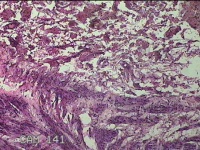

直肠粘膜

性别

女

年龄

31岁

临床诊断

混合痔

一般病史

反复肛门肿块、出血2年。

标本名称

大体所见

灰白暗红色条索状组织4.5x1.3x0.8cm一块,表面糜烂,切面灰白暗红色,质软。

似痔。